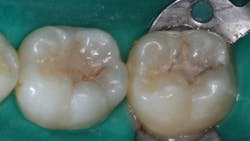

This is, perhaps, the most important reason for sealant failure. Some clinicians use an explorer to “remove” plaque from the grooves—not remembering that an explorer is at least 100 microns in diameter, and the groove can be as small as a few microns wide at the most apical level (figure 2). What does the explorer accomplish? It only pushes more plaque into the depth of the groove.

You can overcome this challenge by using an air polisher (figure 3) to remove the plaque from the grooves. The sodium bicarbonate slurry the air polisher provides is water-soluble. The particles become smaller and smaller as the water is combined with them, thus penetrating to the bottom of the groove and removing the plaque. Another advantage of using an air polisher is that if any color is left in the groove after using it, the likelihood of caries being present is almost assured. In this case, a restoration should be accomplished instead of a sealant.Remaining caries